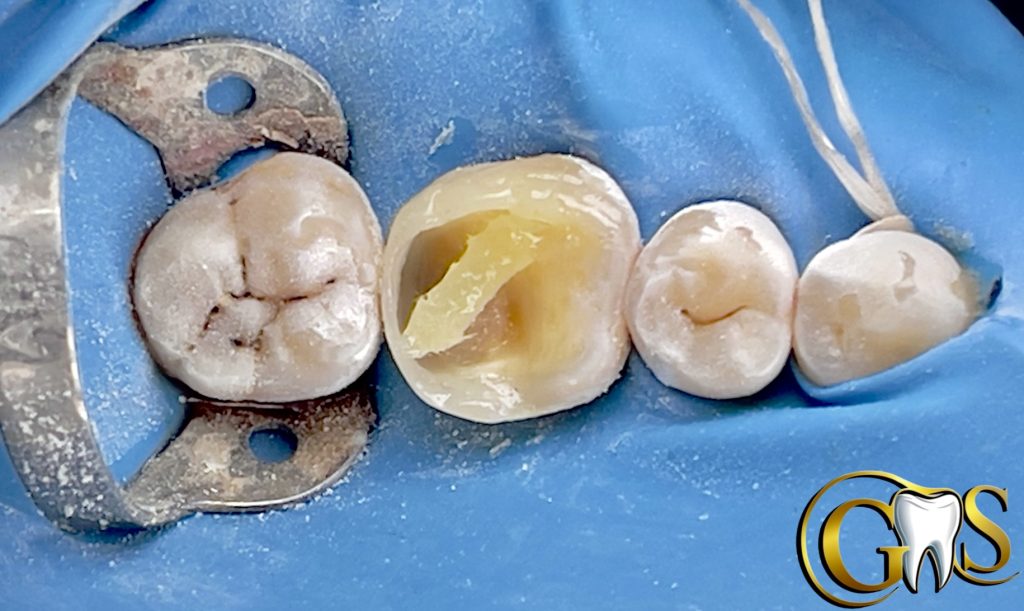

6-DWF (Decoupling with Fibers ) using Ribbond to improve Bonding with affected Dentine and for better stress Distribution

7-Ever X posterior for Dentine replacement (mimic Dentine under stresses)

8-Brown stain

9-finishing and polishing